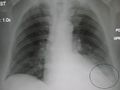

Pneumonia as seen on chest x-ray. A: Normal chest x-ray. B: Abnormal chest x-ray with shadowing from pneumonia in the right lung (white area, left side of image).